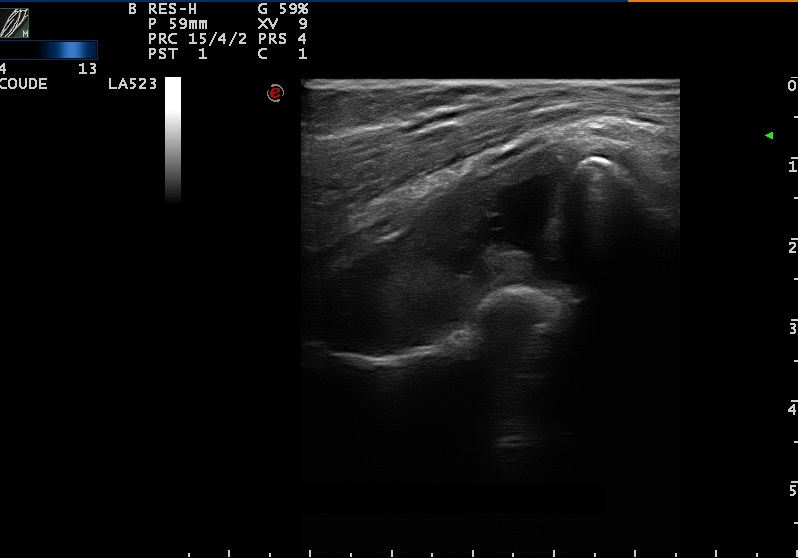

Synovite du coude dans le cadre d'une polyarthrite rhumatoïde évoluée